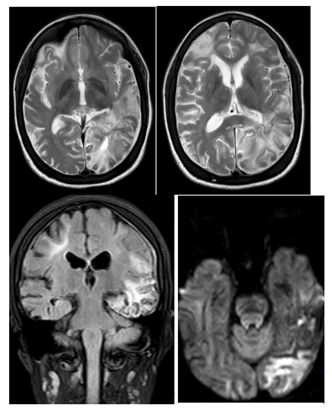

Case N°2

This is a 16-year-old girl, followed for sickle cell anemia since the age of 2years, having an antecedent DALY at 5years of age; who presented a brutal presentation of alertness disorder with right hemicopra deficiency related to left posterior cerebral AVCI. An MRI performed urgently in the three planes of space in weighted sequences T1, T2 FLAIR and angio-RM arterial. It highlights an AVCI range of different age in the most recent is left carotid. The ARM shows the interruption of the two internal carotids at the level of their terminal segment C1, which are of reduced caliber in their intracavalous path with no individualization of the proximal segments of the 2 anterior and posterior cerebral arteries, a fine anastomotic network at the base "pseudomoya" Figure 3 & 4.

Figure 3 Angioplasty MRI performed in emergency: in the 3 planes of space in T1, T2, FLAIR and arterial angio-RM: Presence of multiple bilateral hemispherical lesional foci of cortico-subcortical topography in hyper signal T2 and FLAIR , hypo-signal diffusion in the frontal bilateral, parieto-rollodial right and associated with signal abnormalities of the white matter under cortical and gray nuclei bilaterally of chronic vascular pace.with the presence of a beach lesional temporo-parieto-occipital left in hyper signal T2, FLAIR and diffusion b1000, erasing the cortical furrows with mass effect on the occipital intersection.